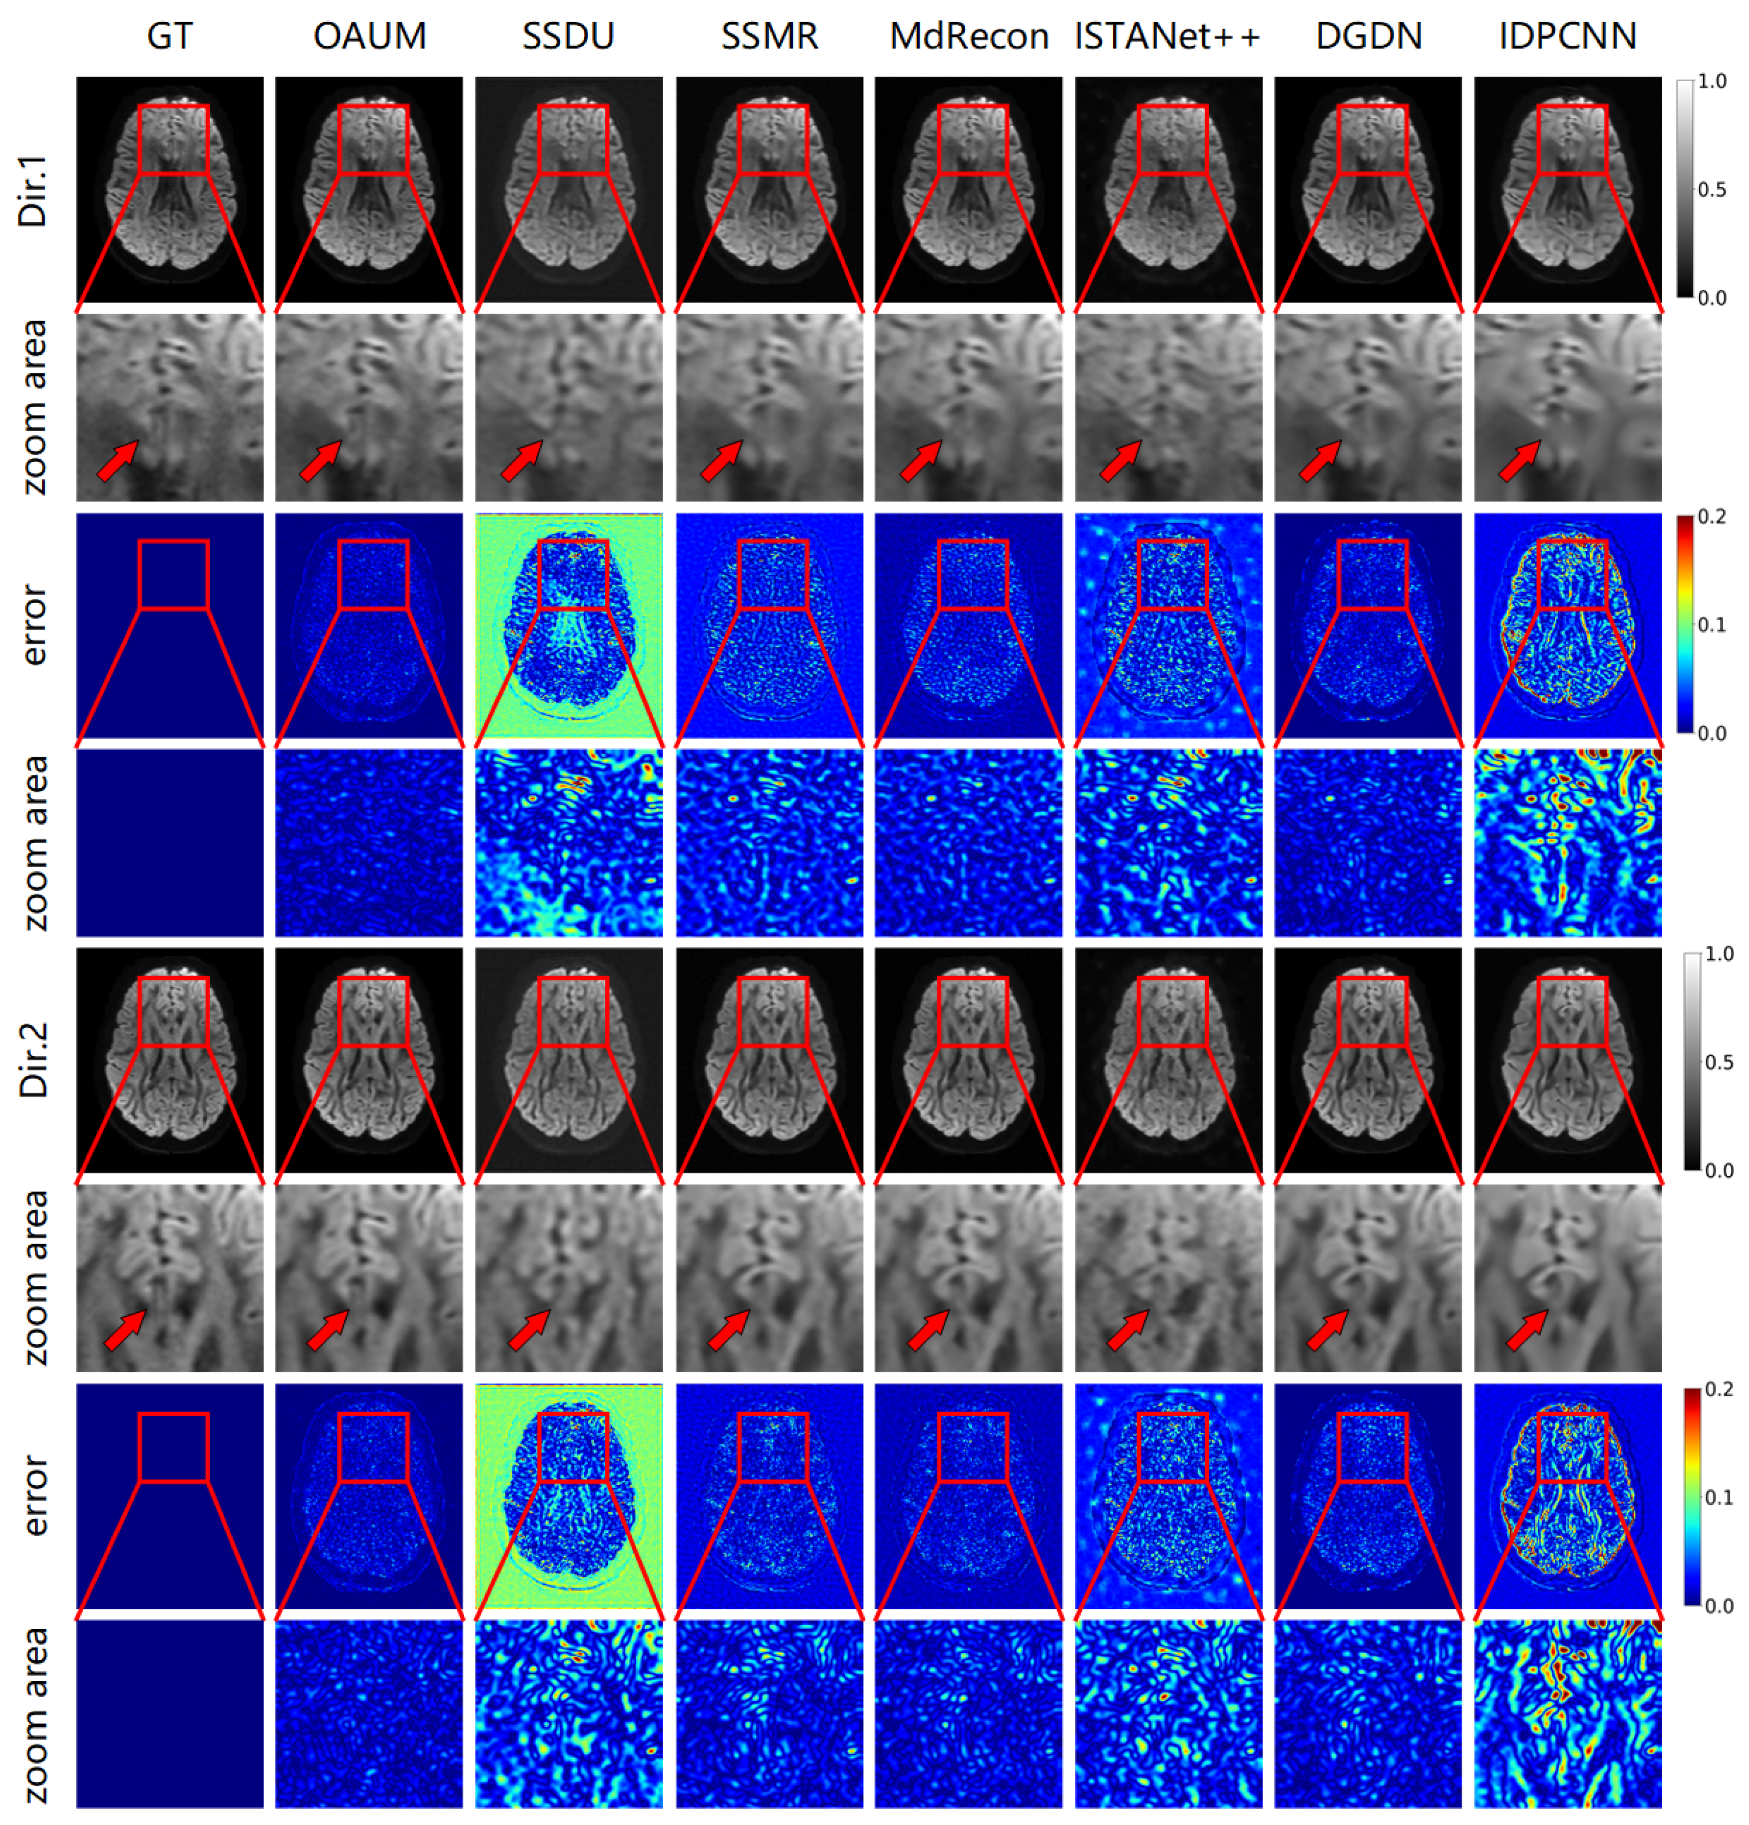

Figure 4 shows the DWIs reconstructed using the proposed model (OAUM) and various comparison models under 4-fold accelerated sampling, along with their respective ground truth (GT) images. For clarity, reconstruction results in two gradient directions are presented in Figure 4, and all results were normalized for consistency. Our method (OAUM) outperforms both self-supervised and supervised methods in terms of image quality improvement in both the gradient directions. Compared to the ground truth full-sampled data, OAUM has the smallest residual error when reconstructing DW images while exhibiting clearer details and textures that can be observed through red arrow areas. IDPCNN and ISTANet++ exhibit poor reconstruction performance at the brain structure edges, while SSDU performs poorly in background regions and skull edges. Although SSMR, MdRecon, and DGDN have acceptable residual ranges, their residual values are still larger than those of our proposed method when compared side-by-side.

Figure 5 demonstrates the reconstruction effect of our model at a higher sampling rate. The figure shows the reconstructed DWIs of each model and its residual images compared to the true fully sampled image at an 8-fold acceleration factor (sampling rate of 0.125). Our method outperformed all other methods in detail recovery, as shown by the red arrow in the DW image. Comparing the Dir.1 and Dir.2 directions, OAUM exhibited a worse performance in the Dir.2 gradient direction than the Dir.1 direction because Dir.2 DWIs were reconstructed from q-space undersampled data. However, compared to self-supervised method SSDU and supervised methods ISTANet++ and IDPCNN, OAUM still had significantly lower errors, demonstrating its superiority.

Figure 4. The DWIs reconstructed from models with acceleration factor (AF) = 4 and two diffusion gradient directions.

Figure 5. The DWI results reconstructed from models with acceleration factor (AF) = 8 and two diffusion gradient directions.